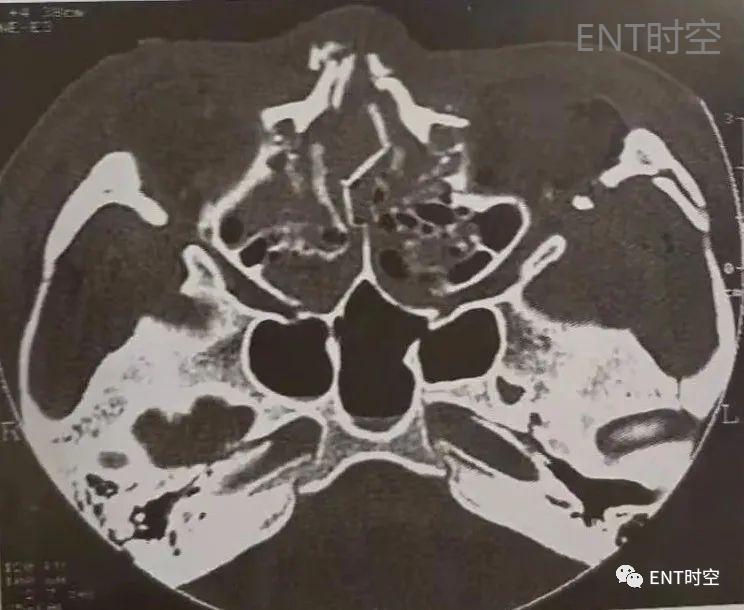

3、筛窦骨折:筛窦位于筛骨蜂房结构中,骨壁菲薄,筛骨纸板构成眶内壁,筛板构成前颅窝底,介于鼻腔顶和筛窦之间。单纯筛窦骨折少见,多为复合性骨折。(图1、2)

图1鼻-鼻窦多发骨折。轴位CT显示鼻骨、右侧上颌骨额突、鼻中隔及眶外侧壁骨折。

图2鼻-鼻窦多发骨折,轴位CT示上颌窦各壁及翼突多发骨折,上颌窦内积血。